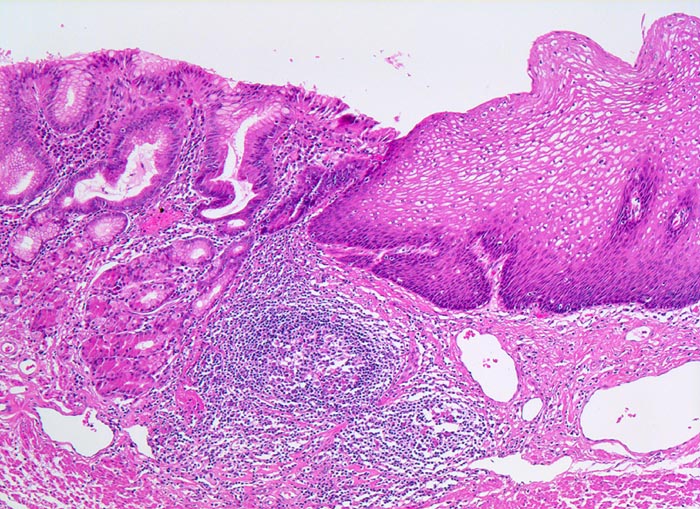

PathoPic – image database / PathoPic ID 4754 - Basalzellhyperplasie bei gastroösophagealer Reflux

Basalzellhyperplasie bei gastroösophagealer Reflux

Ausschnitt aus dem gastroösophagealen Übergang. Rechts im Bild die akanthotisch verbreiterte Ösophagusschleimhaut mit einer Verbreiterung der Basalzellschicht (dunkle Zellen) als Zeichen für Reflux. Daran angrenzend Magenschleimhaut (mit Schleimdrüsen und spezialisierten Magendrüsen) mit geringgradigem Entzündungsinfiltrat im Stroma. Keine intestinale Metaplasie. Lymphfollikel in der Submukosa.

An anderer Stelle im Resektat kann neben schwer dysplastisch veränderter Barrett Mukosa ein Frühstadium eines invasiven Adenokarzinoms nachgewiesen werden.

Morphologische Veränderungen bei Reflux: Hyperplasie der Basalzellschicht (Basalzellschicht normalerweise 10-15% der Schleimhautdicke), Hyperämie und Verlängerung der bindegewebigen Papillen auf >50% der Schleimhautdicke, Granulozyten in der Mukosa (vor allem eosinophile). Die Zylinderepithelmetaplasie und die Barrettmukosa sind ebenfalls eine Folge von vermehrtem Reflux.